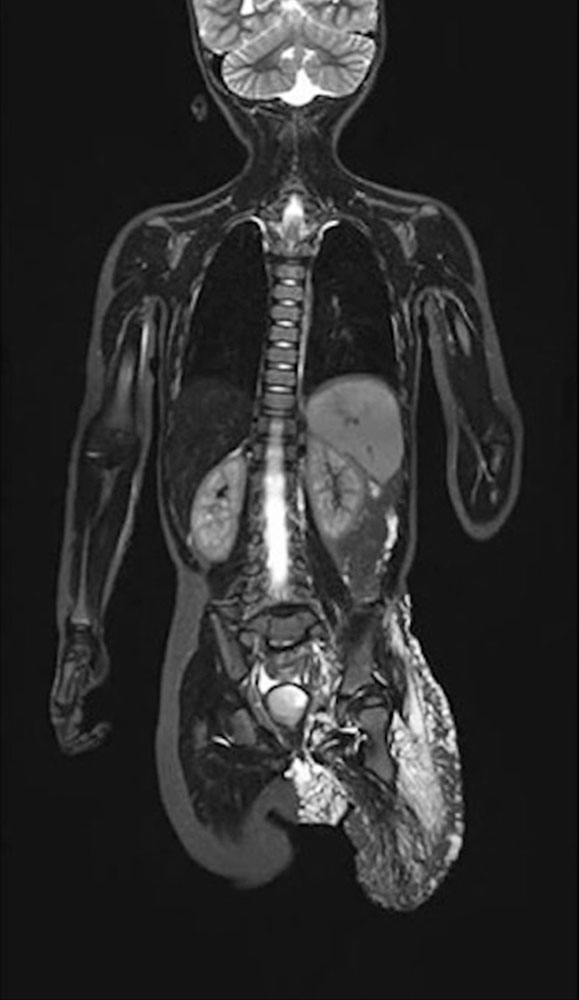

On the other hand, hemihyperplasia or circumscribed overgrowth syndromes and asymmetric hyperplasia syndromes are often associated with scoliosis that may be due to asymmetric growth of the vertebral bodies, analogous to the development of leg length discrepancy. These are to be regarded as syndromic forms of scoliosis.

In CLOVES syndrome, scoliosis is considered a typical concomitant symptom and represents the “S” in the name of this disorder.

In patients with vascular anomalies, diagnosis of scoliosis should usually be further evaluated by MR imaging of the spine to distinguish whether the spinal curvature is due to a vascular malformation in the spine itself (e.g., in CLOVES syndrome) or a possible leg length discrepancy. On the other hand, it may be an idiopathic scoliosis that is present in the patient independently of the vascular malformation.